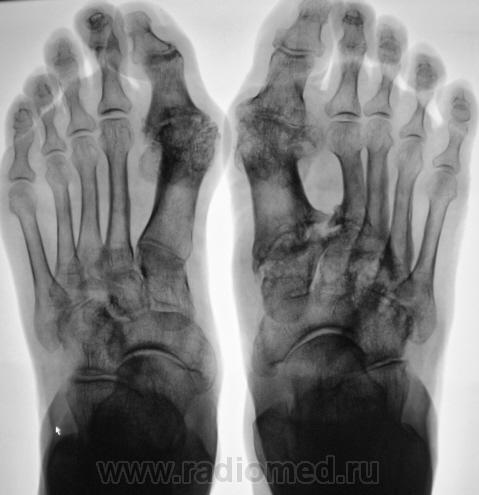

Пациентка направлена на рентгенографию стоп в прямой проекции с диагнохом - "Поперечное плоскостопие".

Произведена рентгенография обеих стоп в прямой проекции.

Думаю, что это дисхондроплазия - болезнь Олье.

Сильно сомневаюсь в болезни Олье - затронуты только суставные концы, диафизы интактны. Считаю - остеоартропатия, вероятнее всего - подагра

Классика подагры - наличие тофусов в параартикулярных мягких тканях... Механизм поражения скелета при подагре - атрофия от давления тофусами. А здесь - их совершенно не видно, мягкие ткани просто отодвинуты, но обьем то их - нормальный...

Согласен с артропатией, но подагра - сомнительно....

Поскольку артропатий великое множество....почему бы и не псориатическая...к примеру. Как там с анамнезом?

Пациентка весьма преклонного возраста - за 70 лет.